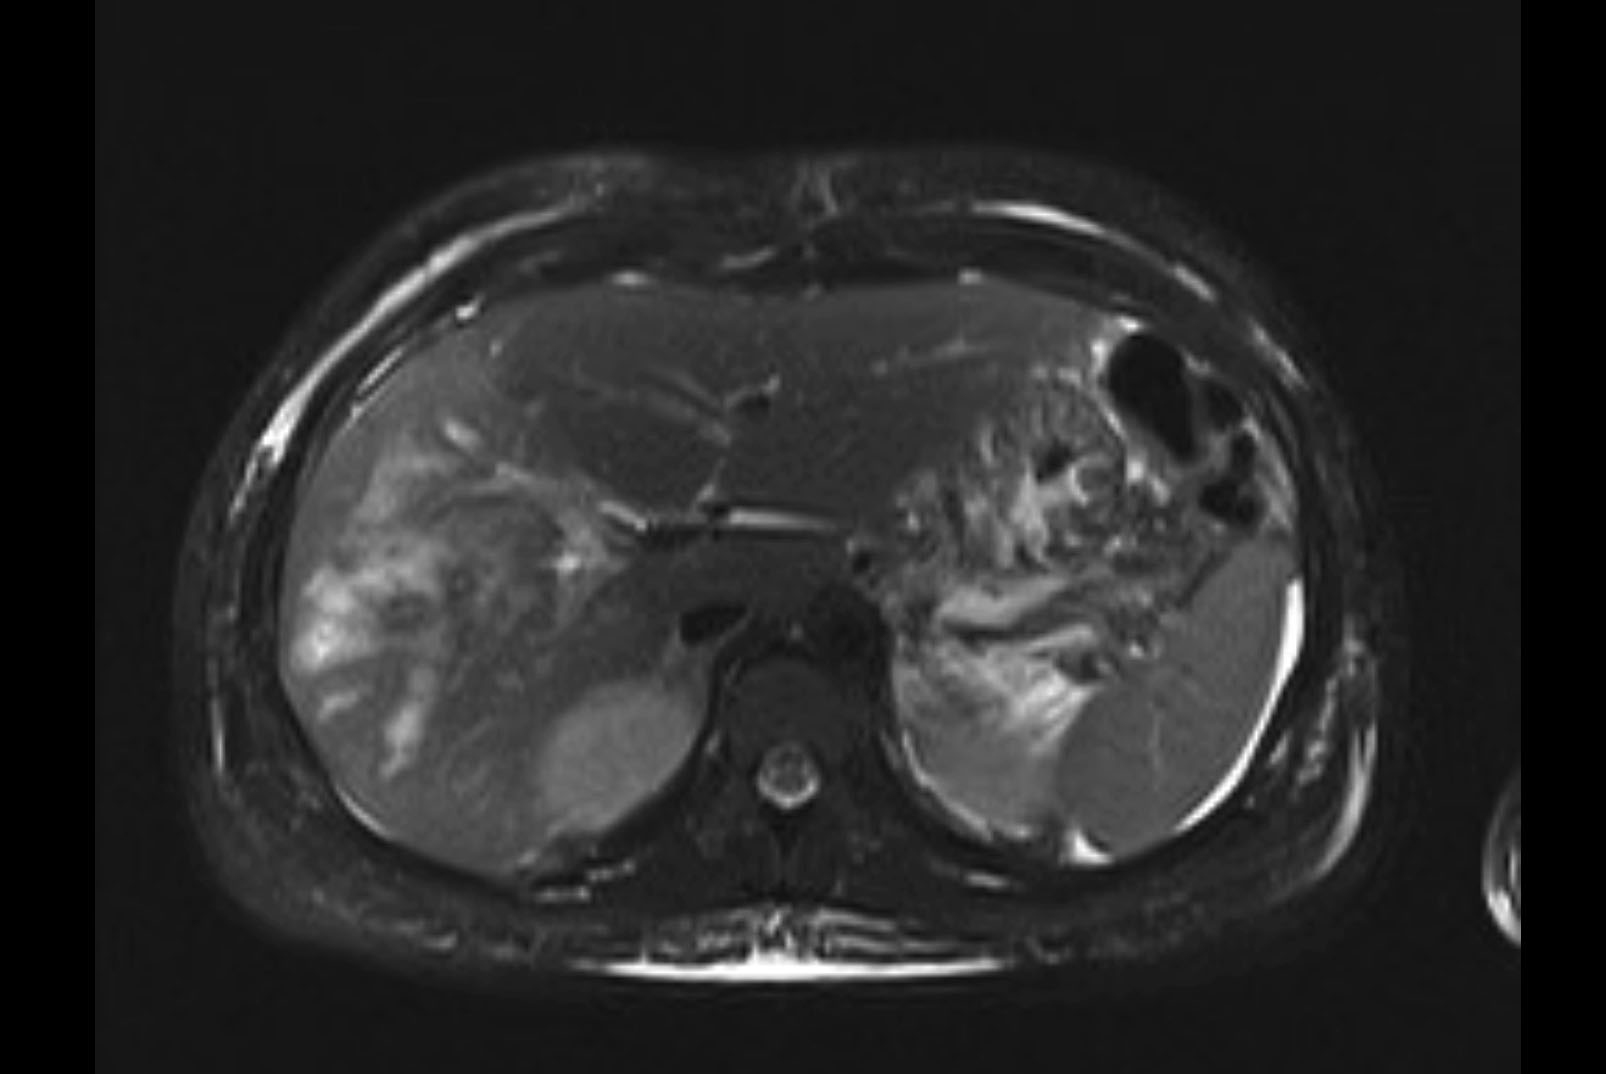

MRI T2